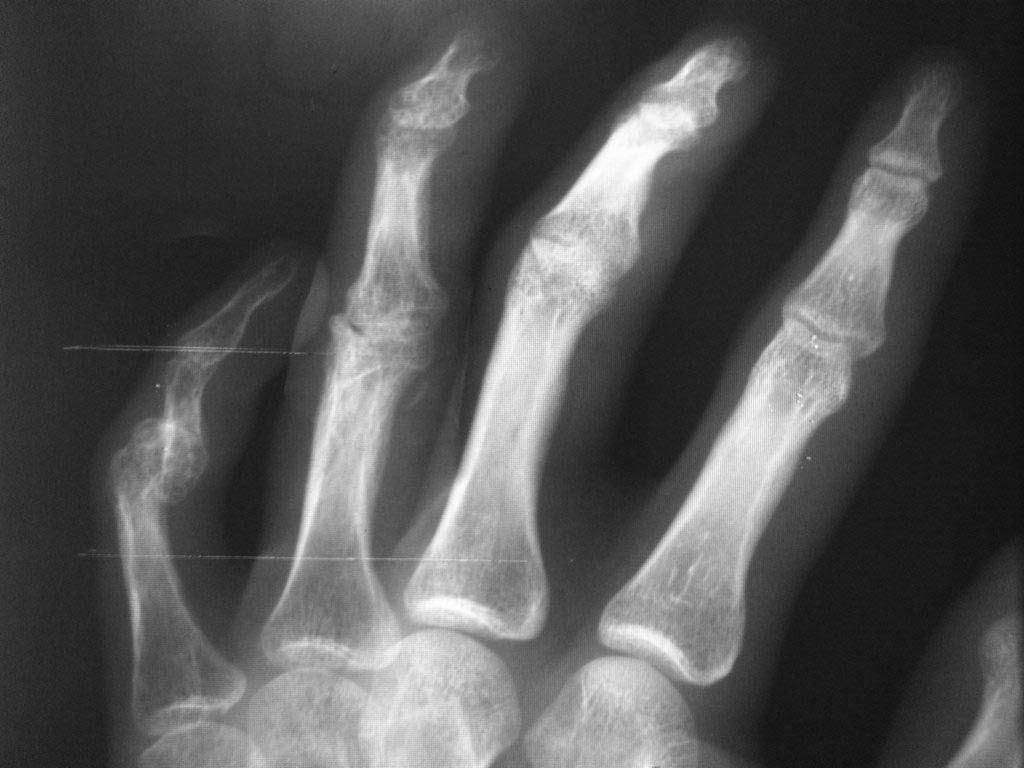

Уважаемые Коллеги! Помогите разобраться с диагнозом, из анамнеза молодой человек 27 лет, порезал руку ножом в области 4 и 5 пальцев правой кисти,

в виду особого состояния (запой), только через 2 месяца обратился в одно из травмотделений с резаной раной 4,5 пальцев правой кисти и полным разрывом сухожилий сгибателей, где был произведен неудачно поздний вторичный шов сухожилий сгибателей, после операции стойкая сгибательная контрактура этих пальцев.

Далее он обращаеется в другое травм отделение где просит врача выпрямить ему эти пальцы, что врач и сделал (артродез межфаланговых суставов в нефункциональном положении, а полностью разогнутом, прямом). После этого начинается самое интересное - уже ровно год после этих событий непрекращающее гноетечение из свищей 4 пальца на уровне проксимальной-средней фаланги.

Ему 4 раза в поликлинике и в одном из хирургических стационаров лечили консервативно и оперировали безуспешно от костного панариция.

Когда обратился ко мне на уровне средней фаланги 4 пальца, свищ по ладонной поверхности, типично как при костном панариции (остеомилите фаланги), но когда я посмотрел на снимок костей, то не увидел остеомиелита, небольшой остеопороз, но он не может быть начальным проявлением остеомилита фаланги, так как является временным переходным состоянием секвестрации фаланги и длится не более 2 недель при отсутсвии лечения, а с момента артродеза прошел уже год.

Наводит на мысль про хронический гнойный тендовагинит, но разве так долго может длиться процесс суставного панариция, да и неужели только я не вижу остеомилита? Прилагаю фото и рентгенограмму больного. Если тендовагинит, тогда буду проводить или проточно-промывное дренирование или же ваккумное дренирование после ревизии пальца, сам больной так устал, что просил ампутировать палец.